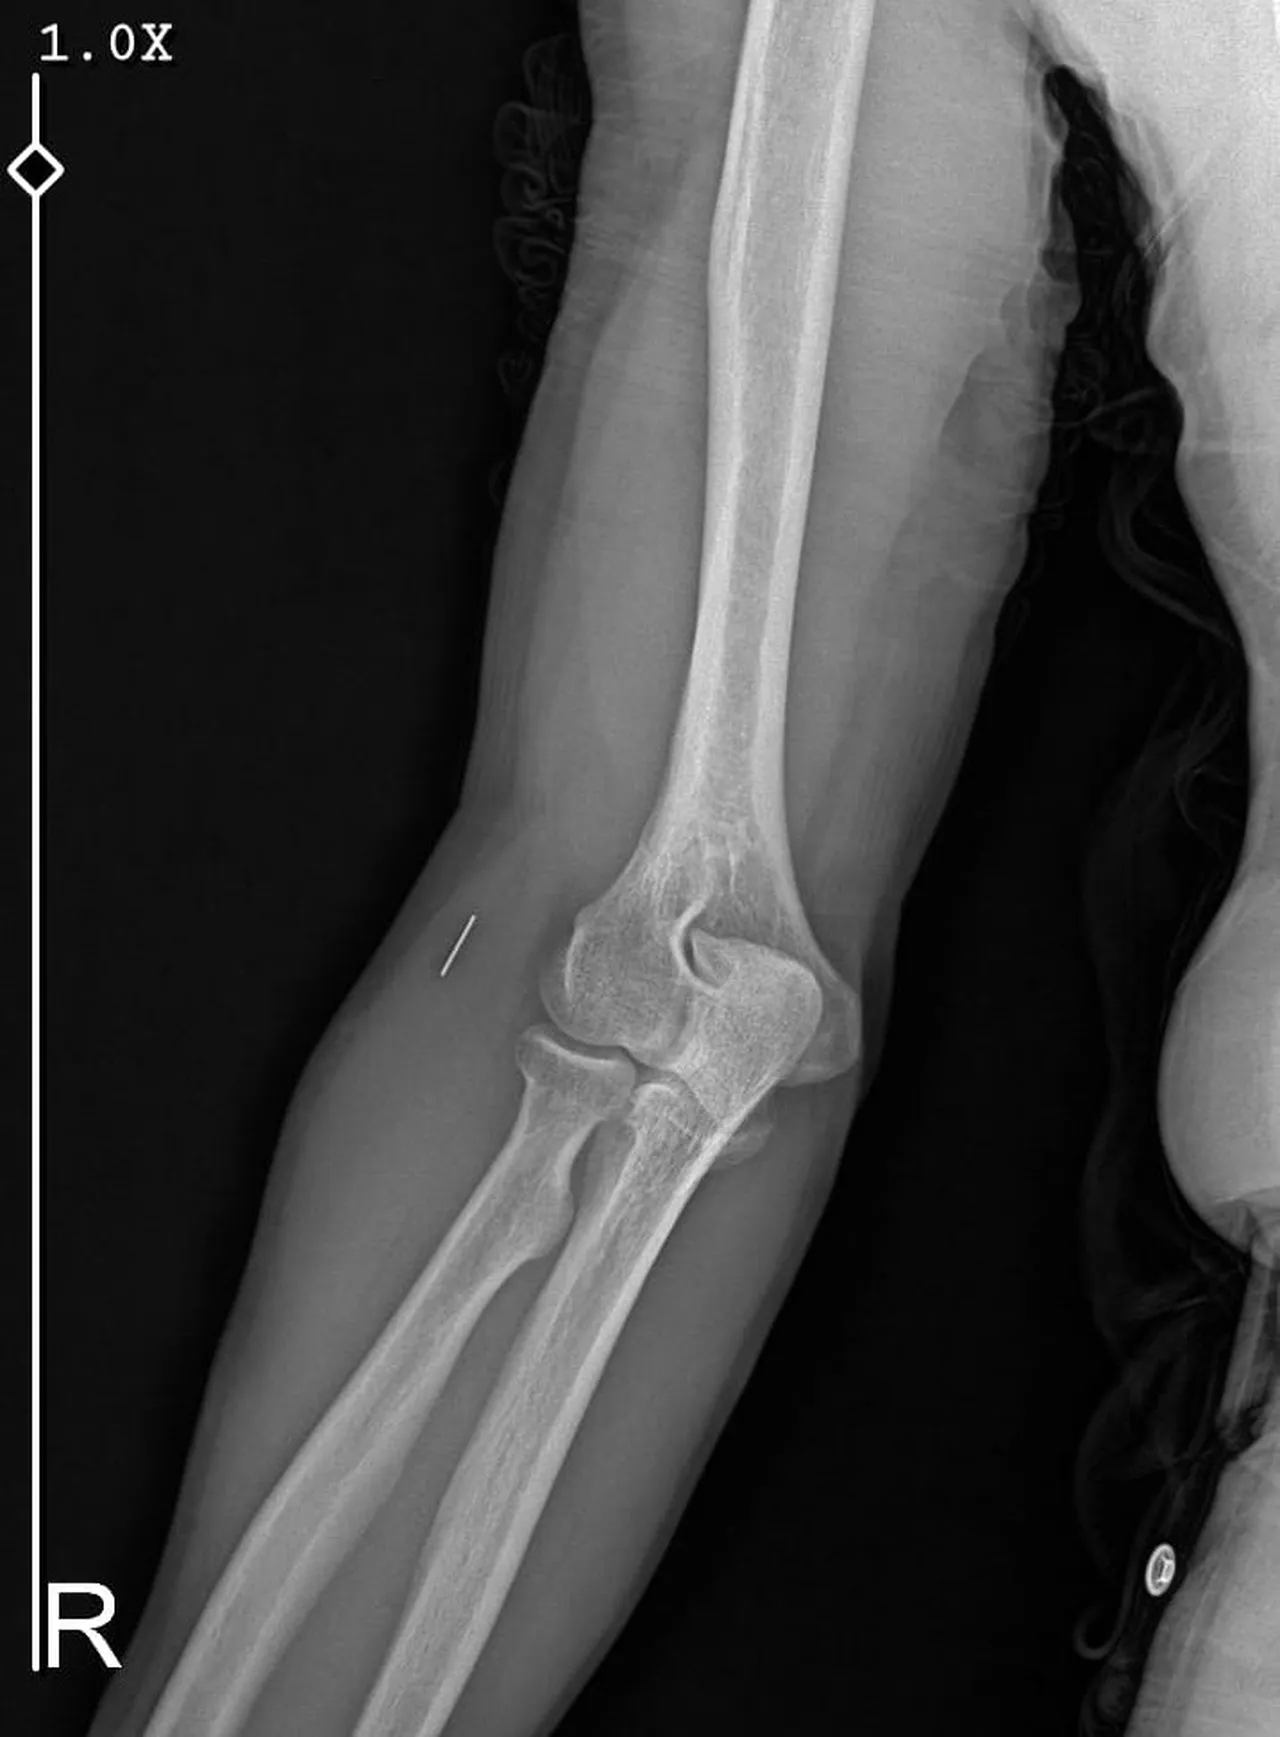

- Ameliyatların ardından kolunda metal parça bulunduğu öne sürüldü ve Güleryüz'ün hastane süreci boyunca işten çıkarıldığı öğrenildi.

Öte yandan, ameliyatların ardından ağrıları devam eden Güleryüz'ün kolunda metal parça bulunduğu ve bu parçanın parmak bölgesinden dirseğe doğru ilerlediği öne sürüldü. Ayrıca, fabrikada temizlik personeli olarak çalışan Nurettin Güleryüz'ün hastane sürecinde işten çıkarıldığı da öğrenildi.

"Doktorlara bileğime doğru ağrılarım olduğunu sürekli ifade etmeme rağmen beni dinlemediler. Sonradan kolumda metal kaldığını öğrendik. Bunun ihmal olduğunu düşünüyoruz. Çünkü kola metal nasıl girebilir? Ben 9 aydır çalışamıyorum. Kalp rahatsızlığım sebebiyle yüzde 46 engelliyken şu anda yüzde 75 engelli durumuna düştüm. Erken emeklilik dilekçesi verdim ancak henüz sonuç gelmedi. Bu konuda çok mağdurum. Yetkililerin bunu duymasını istiyorum. Savcılığa suç duyurusunda bulunduk. Yaklaşık 9 aydır henüz soruşturma izni gelmedi. Süreci bekliyoruz, henüz dava açılmış değil. Kolumda bırakılan metal ilerliyor. Pazartesi günü bunun için de operasyon geçireceğim. Çıkarılıp çıkarılamayacağı net değil. Elimde titremelerim var, çalışamıyorum ve işveren tarafından işten çıkarıldım. Yetkililerden destek ve konunun incelenmesini talep ediyorum."